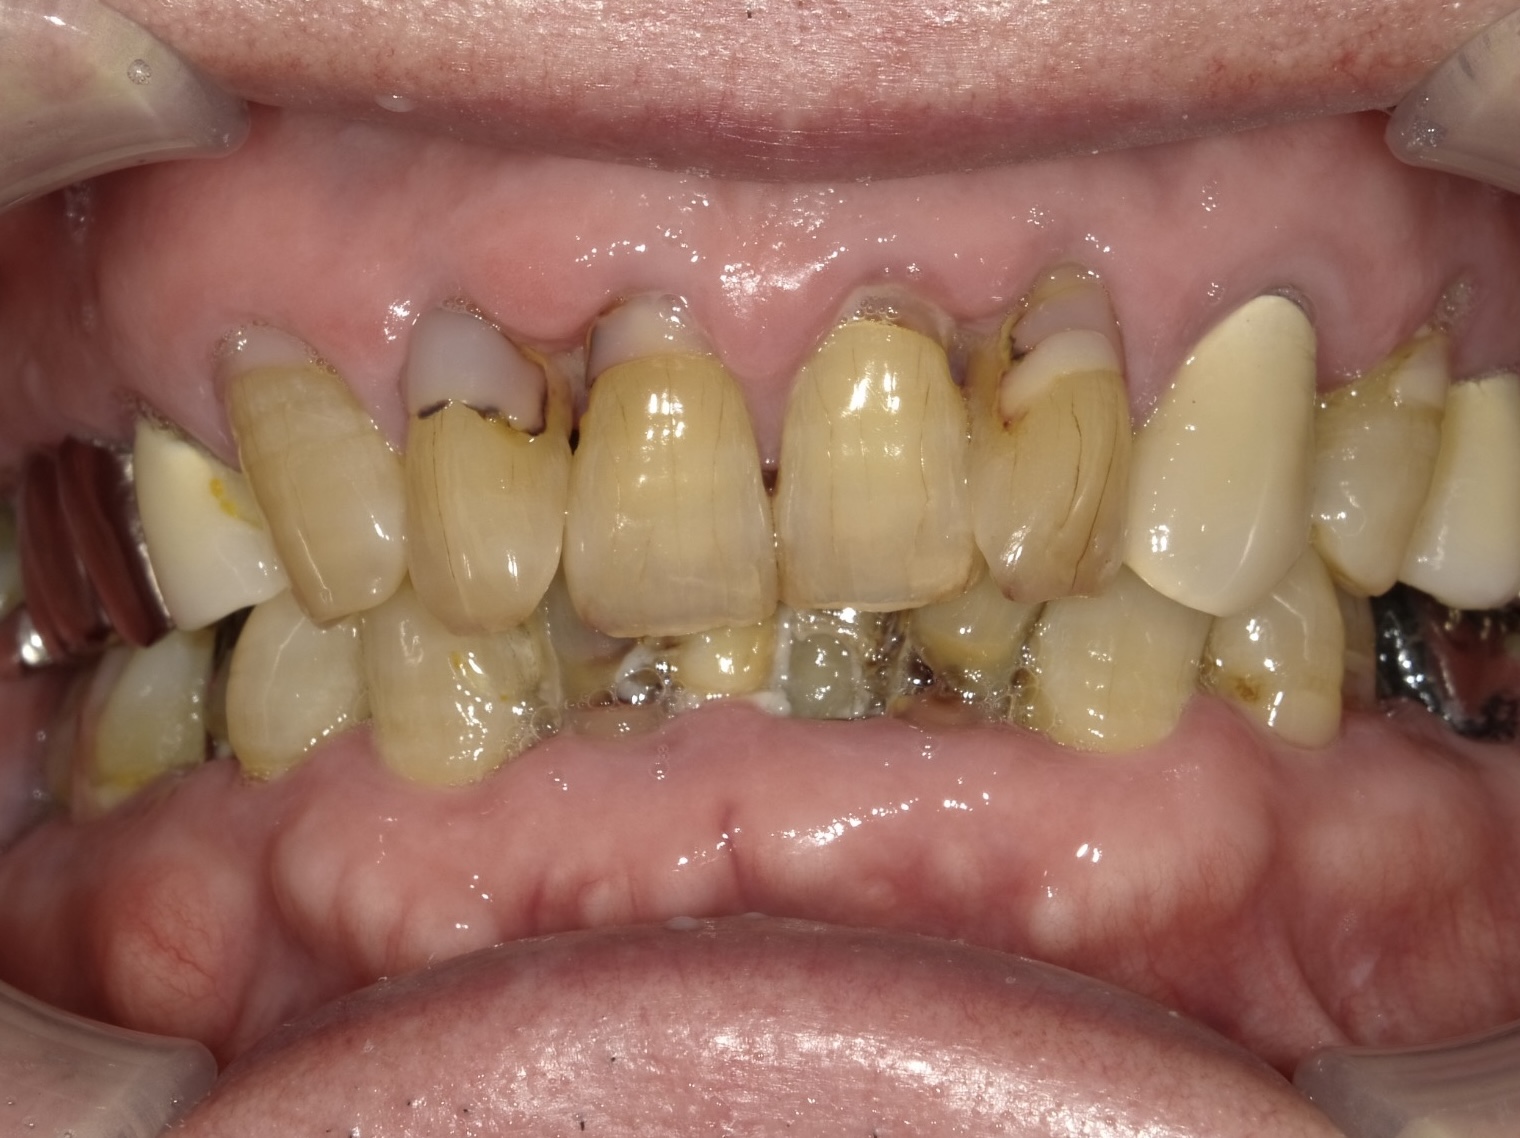

診枚方市藤阪南町にある「藤阪てらしま歯科」は、むし歯や歯周病などの一般治療はもちろん、目立たず歯を美しく整えるマウスピース矯正や、0期から始める小児矯正「マイオブレイス矯正」などの治療にも力を入れています。患者さま一人ひとりに寄り添い、健康で美しい歯をサポートいたします。

虫歯治療decay

歯周病perio

咬合治療occlusion